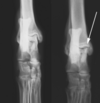

What is seen in these radiographs?

solid periosteal reaction